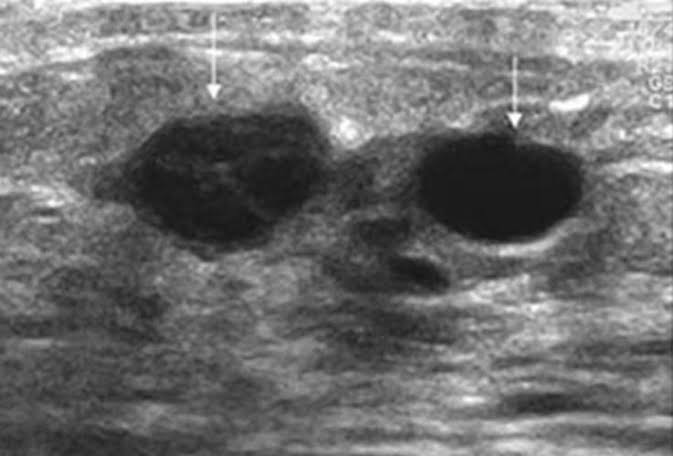

Khalid adds, currently we are focusing on ultrasound, which is a relatively inexpensive and readily accessible imaging modality that can be utilized in the evaluation of clinically palpable breast masses. Ultrasound is a painless procedure that uses sound waves to make images of the inside of your body. The sound waves bounce off surfaces in your body, and the "echoes" are recorded and transformed into video or photographs. It’s often used in addition to mammography to tell whether a lump in a breast is a cyst (a fluid-filled sac) or a solid mass, which might be cancer. This will also help pinpoint the position of a tumor. There is no need for a manual review by a radiologist. Remote diagnosis is made possible if second opinion is needed. Oncologists or radiologists can access from anywhere, anytime.